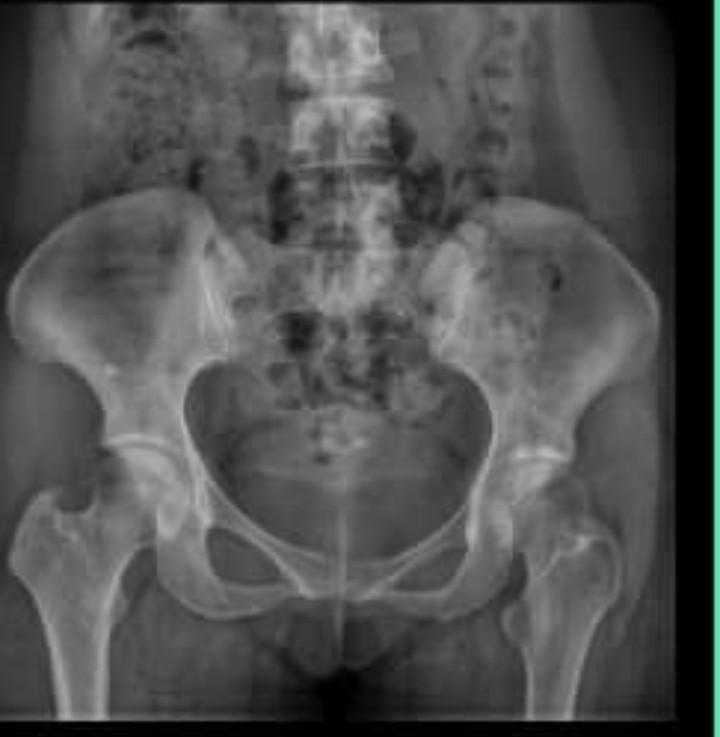

سلام ۱۰روزاست که پای چپ بی دلیل ازلگن تاانگشتان پادردگرفته این ونقطه ی دردمتغیراست بعلت دردشدیدیدتوانایی غلتیدن ایستادن ندارم به سختی راه میروم ودردتشدیدمشودونشستن وبرخاست بادردشدیدهمراه است باتوجه به عکس استخوان لگن سمت چپ دچارآسیب شده؟